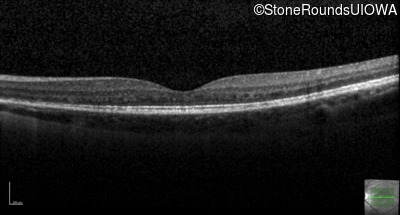

Optical Coherence Tomography - Right - 20/40 +1

Exemplar / OCT Stack